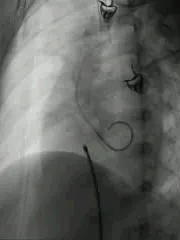

二次术中影像

在术中进行二次超声会诊后,手术团队进行研判,调整了策略,并进行了二次尝试。

建立输送轨道

建立股动脉-VSD-股静脉轨道,沿泥鳅导丝送7F输送鞘至左室,选择6mm对称型、腰高7mm全降解封堵器。

左右盘面展开并锁定

左侧伞盘出鞘为球状,牵拉成型线后形态佳,后展开右盘,封堵器呈现“长哑铃状”,主动脉瓣少量反流。

轻轻牵拉成型线使封堵器成型,牵拉后左伞盘被拉进瘤腔内。

左右盘展开后,封堵器未锁定时造影可见封堵器中间少量反流,主动脉瓣少量反流。

牵拉成型线锁定后,分流消失,主动脉瓣反流消失。

封堵器锁定后呈“蝴蝶状”明显盘状形态,室水平分流完全消失,主动脉瓣反流消失。